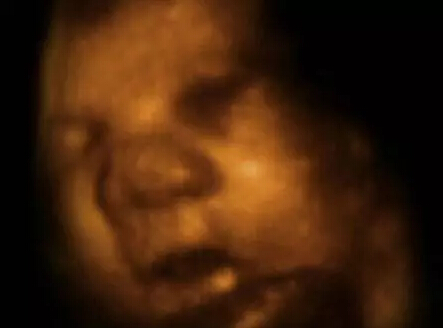

从4-D扫描图的特写镜头可以看到,这个差不多足月的胎儿在吸食羊水。这有助于胎儿为迎接子宫外的生活锻炼消化系统。

看到他们脸部表情的细节,比如微笑和眨眼,还有多胞胎之间的互动,都让我感到非常震惊。“